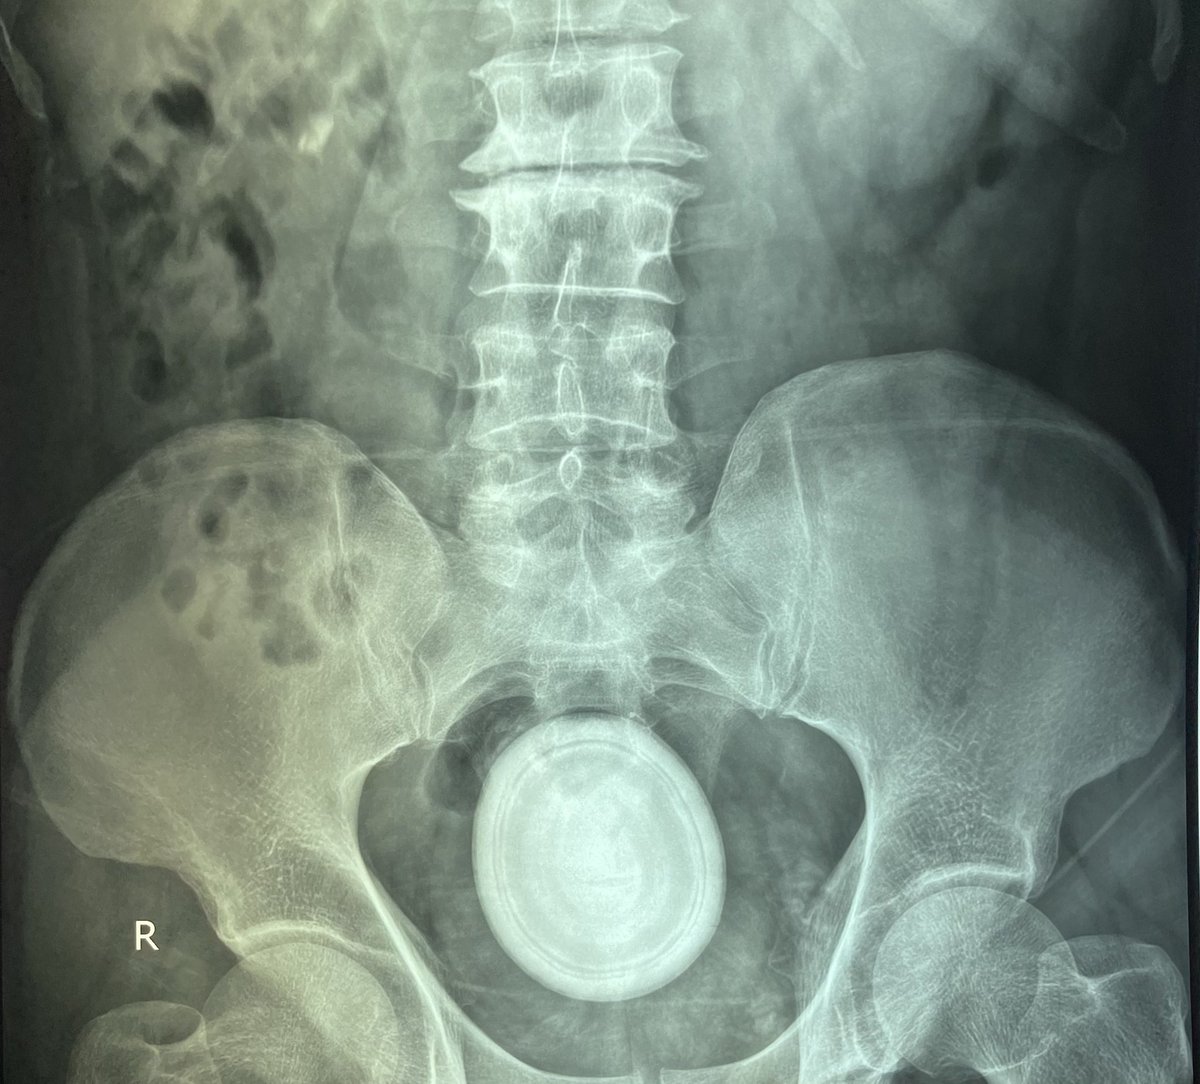

شاهد هذا #الحجر_الضخم في #المثانة البولية يقفز من #المثانة! 🚀 كيف يمكنك تسمية ذلك؟

حصوات المثانة أقل شيوعًا من حصوات الكلى. يتأثر الذكور بشكل أكثر شيوعًا. أي انسداد في المسالك البولية أو عدوى مزمنة يمكن أن تسبب حصوات بالإضافة إلى الجفاف.